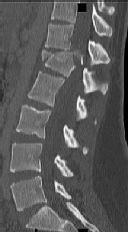

Figures 1 through 3 show the radiograph and CT images of a 68-year-old

woman who sustained a cervical injury after tripping over her cat. She has mild facial trauma, which includes a broken upper incisor and a nonsurgical nasal fracture. She is neurologically intact. Her past medical history is consistent with obstructive sleep apnea, non–insulin-dependent diabetes mellitus (hemoglobin A1c level of 9.0), and morbid obesity, with a body mass index of 40. What is the preferred treatment for this patient?

4. Anterior odontoid screw fixation Discussion: C

Posterior C1-2 fusion with instrumentation provides stability and pain relief with excellent clinical outcomes despite the loss of C1-2 motion. Hard collar immobilization and halo vest immobilization both carry a substantial risk of nonunion in this patient because of her age, fracture displacement, residual fracture gap, and medical condition. Anterior odontoid screw fixation theoretically preserves C1-2 motion. In this case, the fracture is not reduced. Concentric reduction is a requisite for osteosynthesis of the odontoid. Her body habitus also may not allow anterior odontoid fixation.